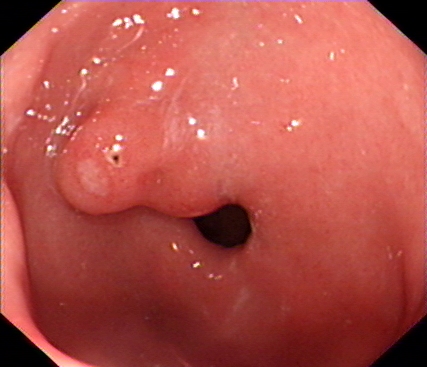

图4 术后三月、6月复查胃镜